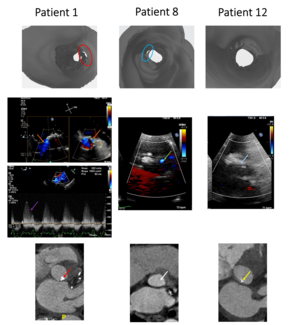

Muhammad Moolla, MD; Hatem Linjawi, MBBS; Dylan Taylor, MD; Anoop Mathew, MBBS

The author report a case of device-related thrombus complicating transcatheter atrial septal defect (ASD) device closure using the GORE Cardioform ASD Occluder, which consists of a thromboresistant-expanded polytetrafluoroethylene material...